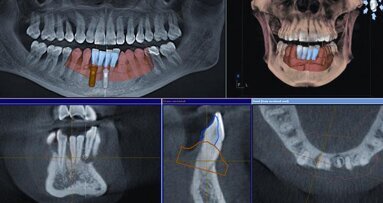

Digital dentistry is coming to the rescue. With Planmeca Romexis, you’re able to combine cone beam data for the 3-D “internal” view of the patient along with intraoral data from the Planmeca intraoral (PlanScan) scans.

Only the Planmeca Romexis combines the data chairside from multiple sources and provides the clinician an intuitive planning process. Planmeca Romexis is an open platform that works with Planmeca and any other dental cone beam manufacturer, such as Imaging Sciences International, Gendex, Instrumentarium Dental and SOREDEX, for a complete solution.

Well, that’s what we can do with Planmeca Romexis—anything we want—at any stage of the game or plan. I can now draw a nerve the same way (using similar tools) as I draw a margin on a preparation. The interface is made for dentistry…for restorative dentistry.

With Planmeca Romexis, I can be flexible because my restoration design and implant placement are both on the same screen, so I can adjust both parameters (restoration and implant) rather than try to heroically save a situation with angled abutments, extensions and other compromises only on the restorative end.

I’ve been lucky enough to be involved and see the development of this exciting software program. It makes everyone’s “wish list” come true. I can draw the nerve(s), view the data from any angle, design the restoration that is right for the edentulous area and then choose one of a myriad of implants to place into the space using just a click and drag of a mouse. Nothing is this easy in dentistry.

Then I can line up the implant with the ideal restorative placement and check the density of the bone and even the angulation of a proposed abutment. Incredible!

“So now we can see the bone available below your tissue. I’m going to combine this data right on this screen and show you what is possible. Here is the implant solution I would recommend, and you can see I’ll place this directly under the restoration we’ve designed and see if you have the type and amount of bone ideal for this procedure.

“We’ll identify the location of the nerve that runs down your lower jaw and certainly avoid that. With this software, you and I can get a great view of the overall process before any treatment is started. So, yes, it looks like this would be an ideal treatment.”